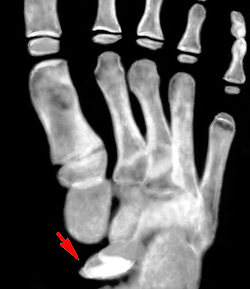

Болезнь Келера-II.

Остеохондропатия головок II или III плюсневых костей. Чаще поражает девочек, развивается в возрасте 10-15 лет. Болезнь Келера начинается постепенно. В области поражения возникают периодические боли, развивается хромота, проходящая при исчезновении болей. При осмотре выявляется незначительный отек, иногда – гиперемия кожи на тыле стопы. В последующем развивается укорочение II или III пальца, сопровождающееся резким ограничением движений. Пальпация и осевая нагрузка резко болезненны.

В сравнении с предыдущей формой данная остеохондропатия не представляет значительной угрозы для последующего нарушения функции конечности и развития инвалидности. Показано амбулаторное лечение с максимальной разгрузкой пораженного отдела стопы. Пациентам накладывают специальный гипсовый сапожок, назначают витамины и физиотерапию.